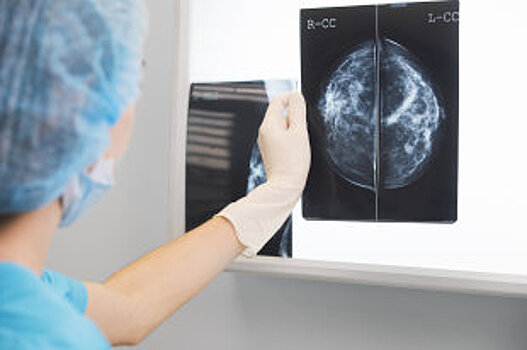

Такие исследования (цитологические, гистологические, молекулярно-биологические и так далее) - являются "отправной точкой" для врачей-онкологов при выборе эффективной тактики лечения пациентов. До сих пор образцы биоматериала для уточняющего диагностирования у специалистов о онкоцентра пациенты привозили с собой, чтобы показать доктору. - Создание специализированной системы позволит врачам областных и городских больниц дистанционно получать заключения более опытных экспертов-патоморфологов без необходимости пересылки стекол и блоков с исследуемым материалом. А значит, для жителей отдаленных городов области онкологическая помощь станет доступнее, - подчеркнул заместитель министра здравоохранения региона Сергей Турков. Ежегодно специалисты центра будут анализировать примерно 15 000 исследований. Кроме того, областные эксперты смогут курировать городские и областные учреждения здравоохранения в период проведения скрининговых программ, а также обучать онлайн специалистов в сфере онкоморфологии. - К единой информационной лабораторной системе референсного центра уже подключились учреждения здравоохранения Нижнего Тагила и Каменска-Уральского. Дальнейшая модернизация технической базы областных медцентров с формированием телекоммуникационных систем и установкой модулей для телеконсультаций позволит присоединиться к системе морфологической диагностики любой областной поликлинике, - объяснил главный врач Свердловского онкодиспансера Владимир Елишев. За последнее полугодие - это уже вторая консультативная площадка, начавший работу в онкодиспансере. В июле был запущен референсный центр лучевой диагностики, где областные специалисты помогают анализировать диагностические данные пациентов (КТ, МРТ) районным специалистам.